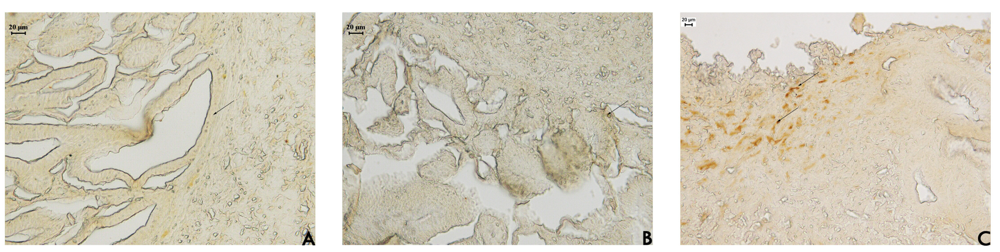

Figure 2. Photomicrography of histological analyses of stomach of rat treated orally with (A) vehicle (10 mL/kg); (B) cimetidine (100 mg/kg); and (C) acetate fraction of Alchornea triplinervia (100 mg/kg). The scale represents 20 μm and arrows denote mucus area by PAS method.

Hayashida et al. [16] observed a notable expression of mucin in regenerating areas in acetic acid-induced ulcers. The mucus bicarbonate barrier is the only pre-epithelial barrier between the lumen and epithelium, and when its breaks down in disease, other intracellular mechanisms come into play [17]. The periodic acid-Schiff (PAS) histochemical method exhibits characteristic carmine staining of stomach regions that secrete mucopolysaccharides. At the end of the treatment period, all stomachs were processed by PAS histochemical analyses. In samples from rats treated with EAF, we observed the intense secretion of mucus in gastric glands (Figure 2) that was absent in sample from the other groups. Mucus production represents one of the main mechanisms of local gastric mucosal defense [17]. A number of factors appear to influence ulcer healing, but mucus and bicarbonate secretion may be important in the ulcer healing process because the mucus/bicarbonate layer protects newly formed cells from acid and peptic injury [18].